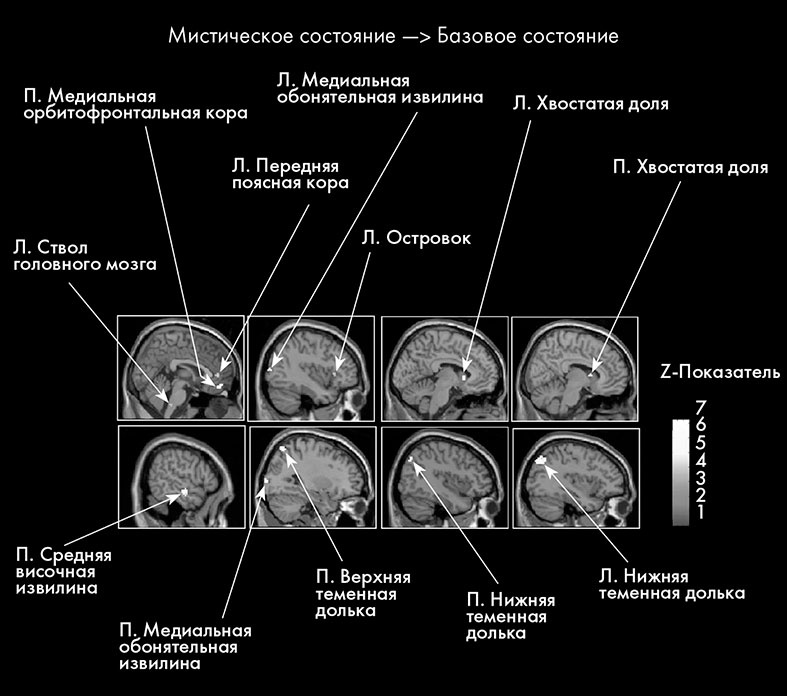

В Исследовании 1 мы проводили сканирование мозга монахинь с помощью фМРТ, чтобы определить, какие участки мозга активны во время мистического опыта. Основной целью этого исследования была проверка гипотезы о наличии «модуля» или «элемента Бога» в височных долях, как предполагают некоторые ученые [863].

фМРТ активизации мозга у монахинь-кармелиток

15 монахинь прошли сканирование, пока они вспоминали и заново переживали свой самый значительный мистический опыт (мистическое состояние), а также самое яркое состояние единства с другим человеком (контрольное состояние), какие когда-либо испытывали за время пребывания в ордене кармелиток [864]. Кроме того, мы проводили сканирование мозга монахинь во время базового состояния – нормального состояния покоя, чтобы оценить активность мозга в привычном состоянии сознания. При всех состояниях глаза участниц были закрыты.